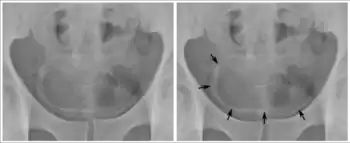

Inflammation and infection

Calcifications on bladder wall caused by urinary schistosomiasis

Cystitis refers to infection or inflammation of the bladder. It commonly occurs as part of a urinary tract infection.[23] In adults, it is more common in women than men, owing to a shorter urethra. It is common in males during childhood, and in older men where an enlarged prostate may cause urinary retention.[23] Other risk factors include other causes of blockage or narrowing, such as prostate cancer or the presence of vesico-ureteric reflux; the presence of outside structures in the urinary tract, such as urinary catheters; and neurologic problems that make passing urine difficult.[23] Infections that involve the bladder can cause pain in the lower abdomen (above the pubic symphysis, so called "suprapubic" pain), particularly before and after passing urine, and a desire to pass urine frequently and with little warning (urinary urgency).[23] Infections are usually due to bacteria, of which the most common is E coli.[23]

When a urinary tract infection or cystitis is suspected, a medical practitioner may request a urine sample. A dipstick placed in the urine may be used to see if the urine has white blood cells, or the presence of nitrates which may indicate an infection. The urine specimen may be also sent for microbial culture and sensitivity to assess if a particular bacteria grows in the urine, and identify its antibiotic sensitivities.[23] Sometimes, additional investigations may be requested. These might include testing the function of the kidneys by assessing electrolytes and creatinine; investigating for blockages or narrowing of the renal tract with an ultrasound, and testing for an enlarged prostate with a digital rectal examination.[23]

Urinary tract infections or cystitis are treated with antibiotics, many of which are consumed by mouth. Serious infections may require treatment with intravenous antibiotics.[23]